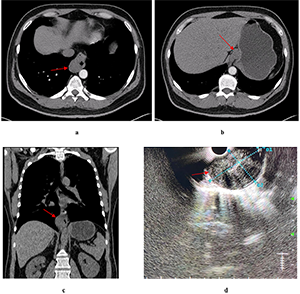

Chest, abdomen, and pelvis CT scan with intravenous enhancement demonstrated a mass originating from the esophageal wall (Fig. 1).

Endoscopic ultrasound (EUS) visualized a hypoechoic lesion originating from the muscular layer of the esophageal wall. The lesion measured 18 mm in basal diameter, extended caudally along the gastric wall, and had a maximum length of 73 mm. It displayed a bean-shaped contour, homogeneous echotexture, and well-defined margins. Fine-needle aspiration biopsy was performed, but did not yield a definitive diagnosis.

On POD 3, the patient developed fever, and subsequent CT revealed bilateral pneumonia and left-sided hydrothorax, prompting modification of the antibiotic regimen.

By POD 6, persistent fever has necessitated transition to broad-spectrum antibiotic therapy with colistimethate sodium and meropenem trihydrate. Nil by mouth was initiated with the switch to parenteral nutrition. An anastomotic leak at the esophagogastric junction was diagnosed on POD 7 via endoscopy, prompting stent placement. Initially, satisfactory stent placement was confirmed by CT. On POD 11, ultrasound detected pleural effusion, which was drained. On POD 13, due to persistent fever, the stent was removed. Further endoscopy revealed a defect involving one-third of the anastomotic circumference. CT demonstrated persistent dehiscence (6 mm) along the posterior wall and a second 4 mm defect, with bilateral hydrothorax and right-sided empyema. On POD 23, endoscopic vacuum therapy (EVT) was initiated under general anesthesia (Fig. 2). The EVT system was replaced ten times over the subsequent six weeks, resulting in gradual improvement. CT and endoscopy confirmed gradual improvement. A final endoscopy showed complete closure of the anastomotic defect with no evidence of passage obstruction. The patient was discharged in satisfactory condition on POD 41 for outpatient follow-up.

Complications included an anastomotic leak at the esophagogastric junction (Clavien-Dindo grade IIIb), bilateral lower lobe hospital-acquired pneumonia, external esophagocutaneous fistula, and mediastinitis.